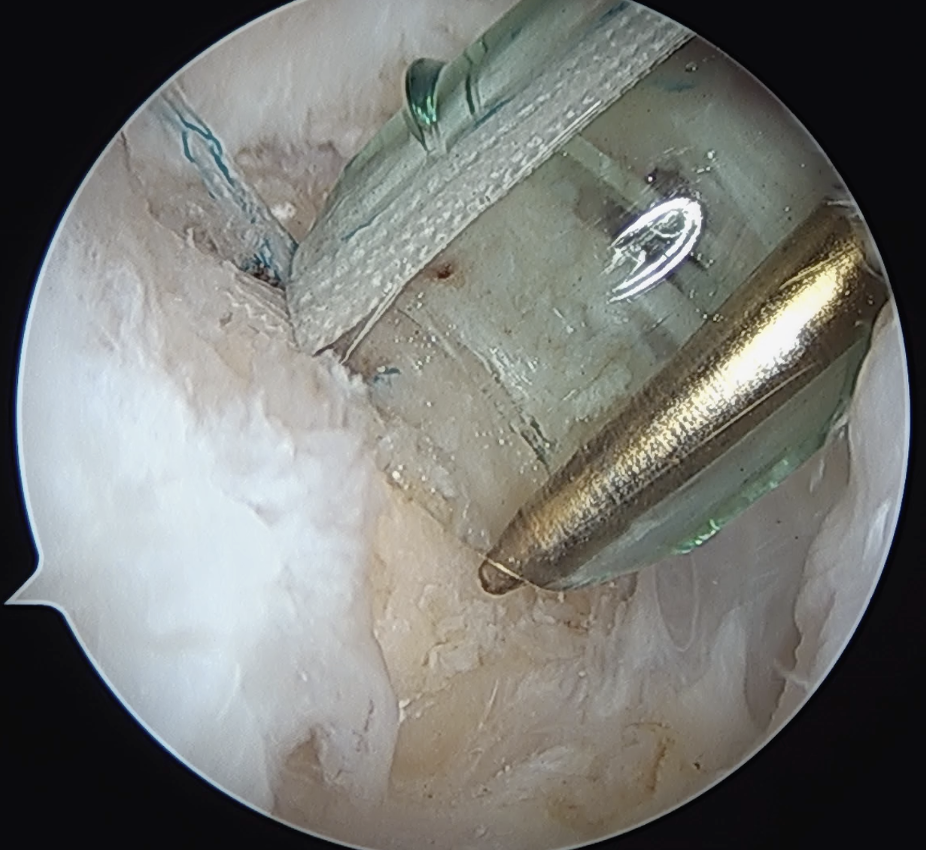

Arthroscopic Suture Bridge Cuff Repair

Arthroscopic Supraspinatous Repair

Technique

Medial row anchors

- inserted through additional stab incision for suture management

- just medial to articular cartilage

Pass sutures through medial cuff tendon

- camera posterior

- suture passer via lateral portal

- retrieve sutures through anterior portal

- repeat

- tie medial row